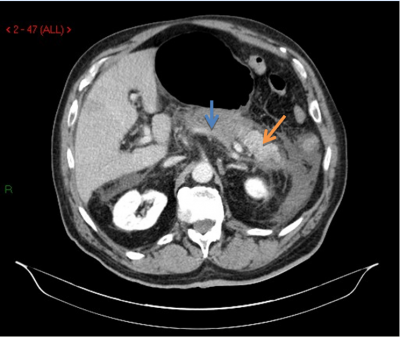

- טומוגרפיה ממוחשבת היא בדיקת הבחירה לאבחון דלקת הלבלב. יש לבצע טומוגרפיה ממוחשבת בחולי דלקת לבלב חריפה שבהם התהליך אינו משתפר במשך יומיים-שלושה, ואם מופיעים סיבוכים או מתקיימים יותר משלושה קריטריונים על-שם Ranson. הממצאים יכולים להיות:

- לבלב בצקתי (תצלום 1.9);

הזילוח של רקמת הלבלב מתבטא בעוצמת ההאדרה לאחר הזרקת חומר ניגוד והתפלגותו בלבלב חשובה. ככל שההאדרה קטנה יותר, כך הנמק בלבלב רב יותר (תצלום 2.9). חולים שבהם נמצא בטומוגרפיה ממוחשבת נמק של יותר מ-50% מהלבלב יפתחו יותר זיהומים מחולים שבהם נמצא נמק קטן יותר, ולכן יזדקקו יותר לניתוחים. יש המבצעים בהנחיית טומוגרפיה ממוחשבת דיקור של הלבלב ושואבים ממנו חומר לתרבית. תרבית חיובית של הנמק מחייבת ניתוח.

- הסתיידויות באזור הלבלב (תצלום 2.9).

בשנים האחרונות משמש הסורק הממוחשב, בייחוד כשהצילום מבוצע בעזרת חומר ניגוד, אמצעי חשוב להדגמה אובייקטיבית של היקף הנמק באזור הלבלב ולאיתור מוקדם של סיבוכים מקומיים עקב התהליך הדלקתי.

Block וחבריו בדקו את יעילות הסורק הממוחשב, לעומת בדיקת על-שמע (אולטרה-סאונד) וניקוד על-שם Ranson, בחולי דלקת לבלב חדה שנותחו בסופו של דבר:

- בבדיקת סורק ממוחשב זוהו 85% מהחולים בדלקת לבלב חדה, כאשר היקף הנמק זוהה ב-72% מהחולים עם נמק מוקדי ו-67% מאלה עם נמק מפושט.

דלקת לבלב נמקית מתפתחת בכ-20% מאלה שאובחנו כלוקים בדלקת לבלב קשה שיש בהם יותר מ-3 קריטריונים של Ranson או יותר מ-5 קריטריונים של Apache II. אין ספק שטומוגרפיה ממוחשבת לאחר הזרקת כמות גדולה של חומר ניגוד לווריד היא האמצעי היעיל ביותר לאבחון מוקדם של הנמק. אזורי לבלב שאינם נצבעים בחומר הניגוד נחשבים נמקיים. ממדי הנמק מוערכים לפי היחס שבין האזור שלא נצבע לבין זה שבו אספקת הדם תקינה. אבחון תהליך נמקי בלבלב מעורר כמה שאלות: האם התהליך מזוהם? האם דרוש ניתוח, ואם כן מתי ואיזה?